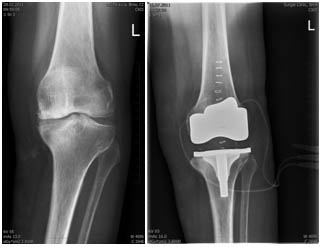

Na rentgenovém snímku se gonartróza projevuje postupným zužováním kloubní štěrbiny, nárustem okrajových osteofytů, subchondrální sklerózou, někdy až tvorbou subchondrálních cyst s možností vzniku nekrózy kosti. Artrózu dělíme dle RTG nálezu na čtyři stádia.

Aloplastika kolenního kloubu je náhrada poškozeného kloubu implantátem, kdy nahrazujeme kluznou část stehenní a holenní kosti.

Femorální komponenta – většinou kovová (CrMoCo ocel), fixována kostním cementem

Tibální komponenta – obvykle z titanu, fixována kostním cementem

Tibiální plateau – polyethylenový kluzný povrch mezi femorální a tibiální komponentou